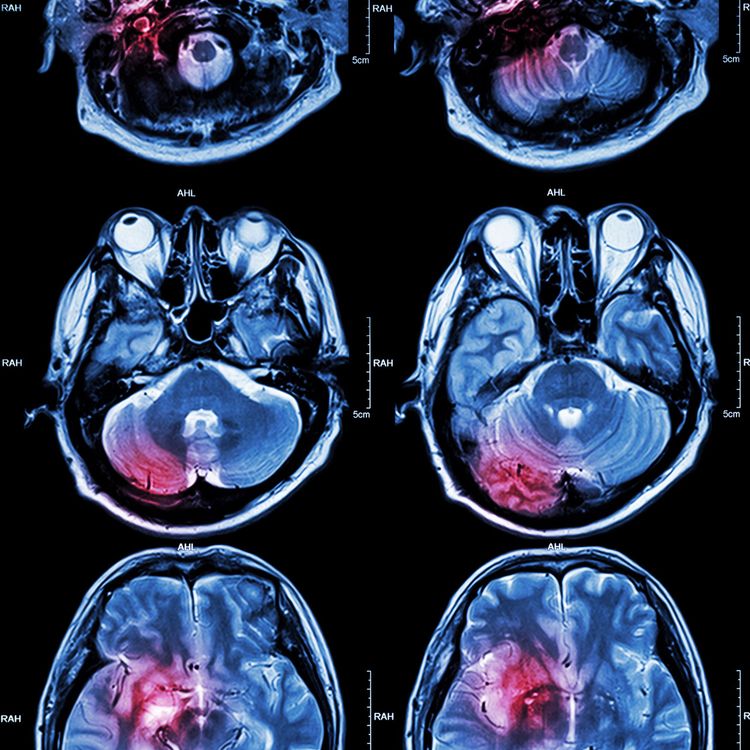

How can we best treat dementia?

Dementia is on the rise, with the numbers affected expected to treble to over 150m in the next 30 years. Clive Cookson discusses the latest treatments with London neurologist Nick Fox, and we hear reports from Edward White and Brooke Fox about initiatives in Taiwan and the US to help improve the lives of sufferers.